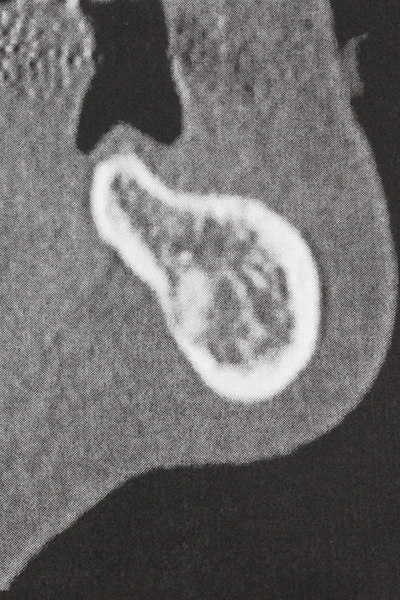

En la cirugía del seno maxilar surgen otros campos de aplicación: En este punto, tras la preparación concéntrica de una tapa ósea de la pared del seno maxilar (que suele tener forma trapezoidal), es posible eliminar patologías y cuerpos extraños del seno maxilar. La tapa ósea se repone después de finalizar la parte intra-antral de la operación y se asegura frente a una posible dislocación mediante cuñas o suturas adaptables.